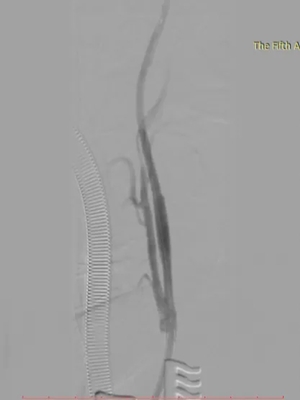

▲ 术后造影

术后,Dr. Ross Milner教授高度评价:“首台手术能在60分钟内成功完成,充分展现了崔文军主任扎实精湛的手术技术、优秀的外科医师素养以及郑大五附院血管外科团队卓越的协作能力。”